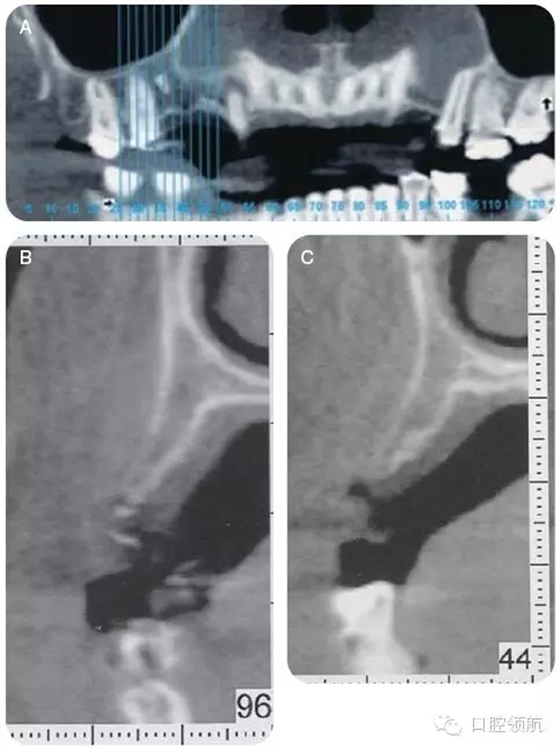

咨詢修復(fù)、牙體牙髓及正畸科,制訂詳細(xì)的治療計(jì)劃。行錐形束CT檢查上頜牙弓,以更好地了解缺損處牙槽嵴的形態(tài)及和上頜竇的鄰接關(guān)系(圖4)。

CT顯示牙槽嵴的垂直距離足夠,為更好地植入種植體,尚需有6~7mm的骨寬度。該區(qū)域的最終治療計(jì)劃包括:引導(dǎo)骨再生,修復(fù)以及咬合重建,包括#4-X-6種植體支持的局部固定義齒。

圖4 (A~C)CT檢查,顯示14號(hào)牙(左上頜第一磨牙)的牙槽嵴水平缺損。